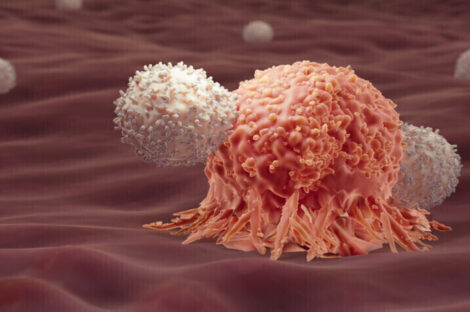

تطور طبي يوصف بالاختراق الثوري، حيث أعلن باحثون من جامعة رايس في تكساس عن تطوير علاج جديد للسرطان يعتمد على…

كشفت دراسة حديثة أجراها مركز أبحاث السرطان في جامعة فيينا الطبية عن اختراق علمي محتمل قد يغيّر جذرياً الطريقة التي…

شهد المجال الطبي تطورًا ملحوظًا مع الإعلان عن علاج مناعي مبتكر لمرضى سرطان الرأس والرقبة، والذي أظهر نتائج واعدة في…